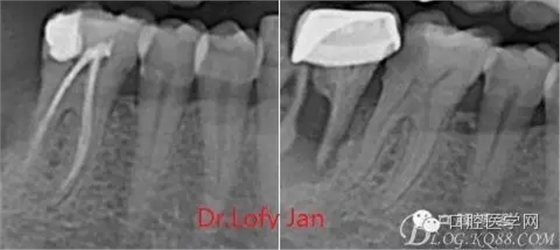

根管治療術(shù)是牙體牙髓疾病治療中最復雜和最關(guān)鍵的治療項目。根管充填材料抵達根尖、并能嚴密堵塞根尖孔,是確保根管治療效果的關(guān)鍵指標。為了保證根管充填到位,醫(yī)生需要在術(shù)前照牙片以了解牙根根管的數(shù)量、彎曲程度和長度,在術(shù)中有時需要插針照牙片來精確測量根管長度,術(shù)后必須照牙片以確定是否根管充填到位,如果欠填或超填,就需要重新充填、重新照牙片確認,直到根管充填到位。所以,在患者接受根管治療時有時會反復照牙片。

病例分析:曲面斷層片在x線輔助診斷與檢查中目前大多數(shù)文獻和著作都建議只能作為初診拍片檢查手段,不能作為終末疾病的確診與手術(shù)療效的評價指標,臨床大部分中小型門診都因為設備不齊全導致信息偏差很大。